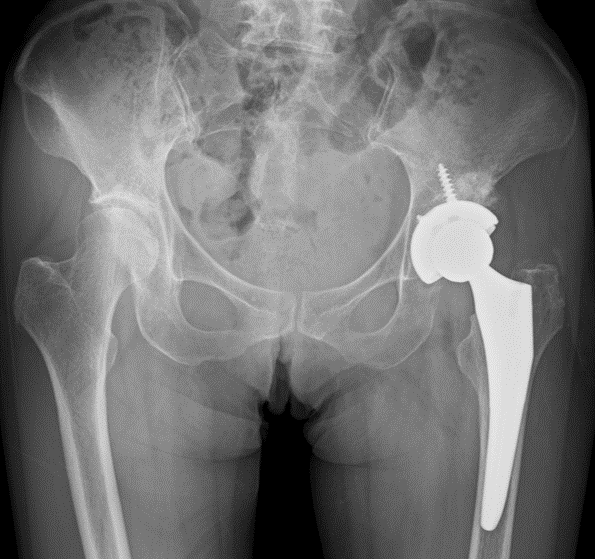

西宮病院 人工関節センターを新設(整形外科)

西宮病院では今年11月、「人工関節センター」を新設しました。人工関節センターでは、整形外科がリーダーとなり、麻酔科、リウマチ科、栄養管理部、リハビリテーション部と密に連携して診療にあたります。

質の高い人工関節手術(股関節、膝関節)を行うとともに、手術だけでなくリハビリや栄養管理等まで、患者様をトータルサポートいたします。

人工関節センターについては、西宮病院のホームページ(外部サイトへリンク)に掲載されているほか、広報誌「はまかぜVol.47(PDF:3,302KB)」の1ページでも紹介されています。

人工関節の写真 |